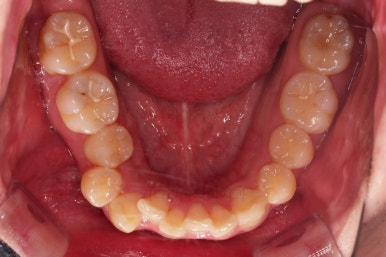

부산교정치과 초진 시 입안의 모습입니다.

앞니가 삐뚤어서 결손치아가 없었더라도 교정치료를 원하셨던 상황이었고요.

오른쪽 어금니 맞물림은 결손치아도 그렇지만 전반적인 앞뒤 차이가 있는 부정교합이 있었어요.